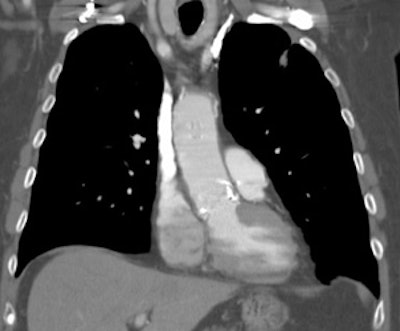

Vascular graft activity: The patient below had a prior graft repair of an ascending aortic aneurysm. Tracer uptake can be seen in the ascending aortic graft (black arrows). The patient also has a left upper lobe lung cancer (red arrows). |

|

Vascular graft activity: Another example of an asymptomatic patient with an aortic stent graft demonstrating tracer accumulation on FDG PET imaging. There is also inflammatory tracer uptake about the hips and left shoulder. |